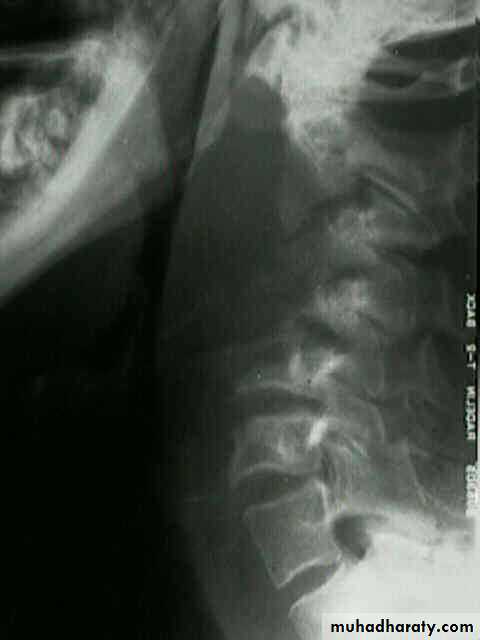

Lateral X-ray of the neck shows evidence of bone destruction and loss of the normal curvature of the cervical spine.

• This is caused by TB of the cervical spine.

• Clinical Picture• Occurs in older children, adolescents and adults. It’s of slow onset and presents as:

• -Pharyngeal discomfort rather than pain.

• -Mild dysphagia.

Chronic Retropharyngeal Abscess (Potts Abscess)

Examination

1. Painless swelling on the posterior pharyngeal wall.2. Enlarged and painless cervical lymphadenopathy.

Investigations

Chronic retropharyngeal abscess